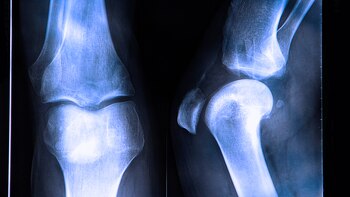

El ligamento cruzado anterior es una estructura que se encuentra en el interior de la articulación de la rodilla. Está situado de manera diagonal, a la altura de la mitad. Se junta con el ligamento cruzado posterior formando una "X" y entre ambos controlan el movimiento de la rodilla hacia atrás y hacia adelante. Previene que la tibia se salga de posición y provee estabilidad rotacional a la rodilla.

Al diagnóstico se llega con el exámen físico, mediante las maniobras semiológicas y la resonancia magnética. Los métodos por imágenes son imprescindibles para la confirmación y evaluación del resto de las estructuras (meniscos, hueso). Para una mejor visualización, la resonancia magnética debe efectuarse en un equipo de alto campo (1.5 tesla o 3 tesla) que permiten ver lesiones óseas en meniscos u otros ligamentos en profundidad.